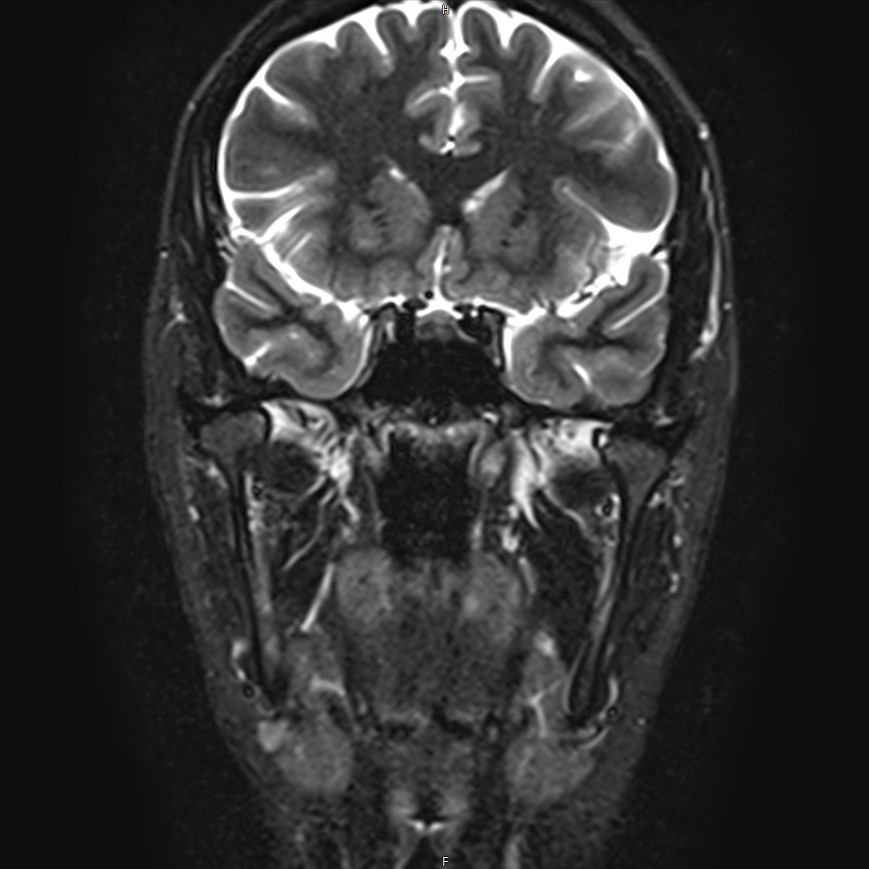

Магнитно-резонансная томография является наиболее точным и эффективным методом диагностики поражения височно-нижнечелюстных суставов, так как позволяет получить детальную информацию о состоянии не только костей, но и связочного аппарата, хрящей, менисков, жевательных мышц, окружающих мягких тканей.

В клинике «Доступная медицина» можно пройти исследование МРТ височно-нижнечелюстного сустава на высокотехнологичном оборудовании. Клиника располагает новейшим томографом экспертного класса TOSHIBA VANTAGE TITAN 1,5 Тесла, который благодаря высокой индукции магнитного поля позволяет получать изображения исследуемой зоны в мельчайших подробностях. Томограф производит послойное сканирование области сустава и околосуставных мягких тканей, затем с помощью цифровых приложений преобразует полученные данные в трехмерные изображения превосходного качества.

Современные томографы дают возможность обнаружить даже минимальные структурные изменения и начать лечение на ранней стадии болезни.

При проведении магнитно-резонансной томографии на изображениях визуализируются: височная кость, головка мыщелкового отростка нижней челюсти, суставная щель. Помимо костных структур МРТ позволяет оценить состояние мягких тканей – внутрисуставного диска и связочного аппарата височно-нижнечелюстного сустава, жевательных мышц.